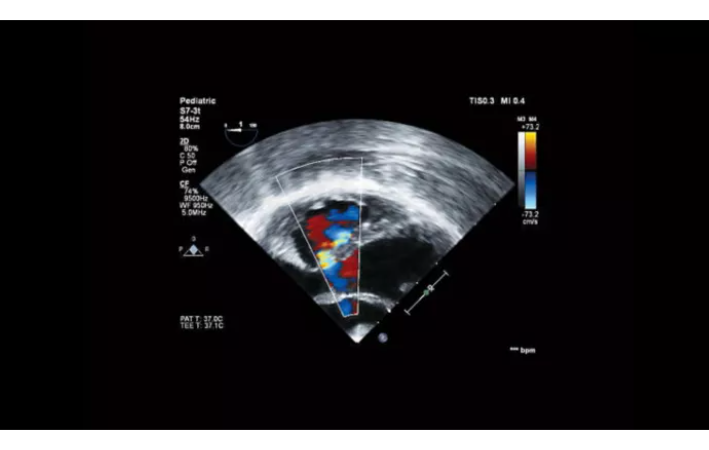

Функции для кардио-исследований

- Stress Protokol - стресс эхокардиография

- GI 3DQ - количественный анализ 3D

- TDI - тканевый допплер

- Strain Q - функция для оценки скорости движения стенок миокарда

- A2DQ - автоматическое распознавание границ камер сердца и расчет площади, объема левого желудочка и параметров систолы и диастолы левого желудочка, расчет фракционной площади, фракции выброса, максимальной скорости выброса, максимальной скорости быстрого наполнения и фракции предсердного наполнения

- aCMQ - Анализ параметров общей и конкретной сократимости камер сердца

- MVI - функция для точной визуализации микрососудов при помощи картирования прохождения контраста по сосудам

- Contrast Card - функция для отображения микропузырьков в миокарде при введении контраста для анализа микроциркуляции в ЛЖ

- a2DQ LA - функция автоматического/полуавтоматического распознавания границ левого предсердия